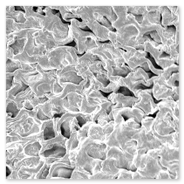

1. Scanning Electron Microscopy Processing unit

Electron Microscopy (EM): Basically two types:

1. Transmission Electron Microscope2. Scanning Electron Microscope

1. Transmission Electron Microscope (TEM) processing unit2. Scanning Electron Microscope (SEM) processing unit3. Ultra Microtome and Histopathology4. Experience in the field of specimen preparation for past 16 years